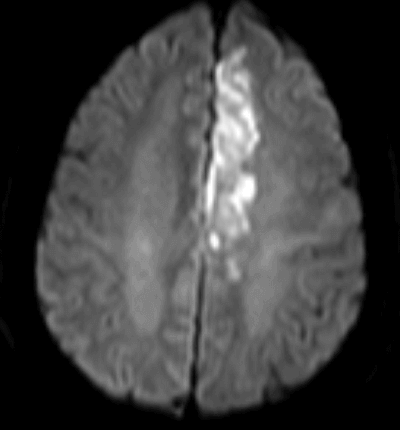

Image caption: Diffusion weighted MR image showing an acute ischemic infarct of the left ACA territory resulting in right leg weakness and an expressive aphasia with intact repetition.

Freedman et al., 1984 describe the anatomical lesions of 15 cases of transcortical motor aphasia, and found that lesions of the ACA in the dominant hemisphere produced a clinically classic TCMA syndrome. The four criteria used by Freedman et al. to identify “classic TCMA” syndromes include limited spontaneous speech, intact repetition, normal articulation, and good auditory comprehension.Since the SMA sits in the ACA distribution, the aphasia that develops with an ACA infarct is attributed primarily to damage to the supplementary motor area (unlike other TCMA syndromes typically thought to be caused by hypoperfusion at the ACA/MCA watershed zone). This type of aphasia can present in the context of typical ACA findings, including: contralateral hemiparesis, with more paresis on the leg than arm, a tendency to look toward the side of the lesion, and a loss of spontaneity.